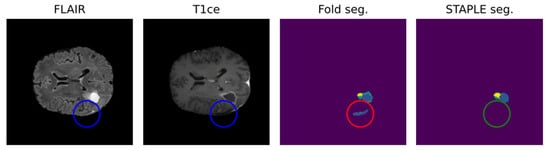

- Visser, M.; Müller, D.; van Duijn, R.; Smits, M.; Verburg, N.; Hendriks, E.; Nabuurs, R.; Bot, J.; Eijgelaar, R.; Witte, M.; et al. Inter-rater agreement in glioma segmentations on longitudinal MRI. NeuroImage Clin. 2019, 22, 101727. [Google Scholar] [CrossRef]

- Sylolypavan, A.; Sleeman, D.; Wu, H.; Sim, M. The impact of inconsistent human annotations on AI driven clinical decision making. npj Digit. Med. 2023, 6, 26. [Google Scholar] [CrossRef]

- Zając, H.D.; Avlona, N.R.; Kensing, F.; Andersen, T.O.; Shklovski, I. Ground Truth or Dare: Factors Affecting the Creation of Medical Datasets for Training AI. In Proceedings of the AIES ‘23: AAAI/ACM Conference on AI, Ethics, and Society, Montreal, QC, Canada, 8–10 August 2023; pp. 351–362. [Google Scholar] [CrossRef]